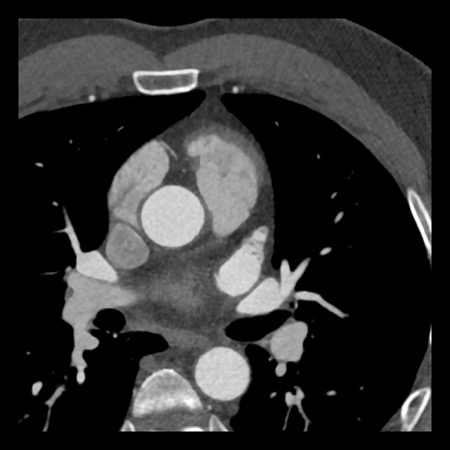

case 2 – CAD-RADS 5/P2/S

First, scroll through the CTA images.

How would you describe the findings on the coronary CTA?

The findings are:

- Stent in the mid

LAD with low-attenuation within the stent suggestive of minimal in-stent

restenosis (<25%). Non-calcified plaque distal to the stent

causing mild stenosis (25-49%). Notice bridging on a short segment in

the distal LAD. - Non-calcified

plaque in the LCX causing mild stenosis (25-49%). - Occlusion of the

proximal OM1 branch with distal filling. - Calcified and

non-calcified plaques in the proximal RCA causing mild (25-49%) stenosis. - Total plaque burden

is moderate based on SIS (four segments including proximal RCA, mid LAD, prox

LCX and OM1).

Due to the occlusion of OM1 branch and presence of the stent, this case

reads as CAD-RADS 5/P2/S, which means that this patient needs further

diagnostic workup.